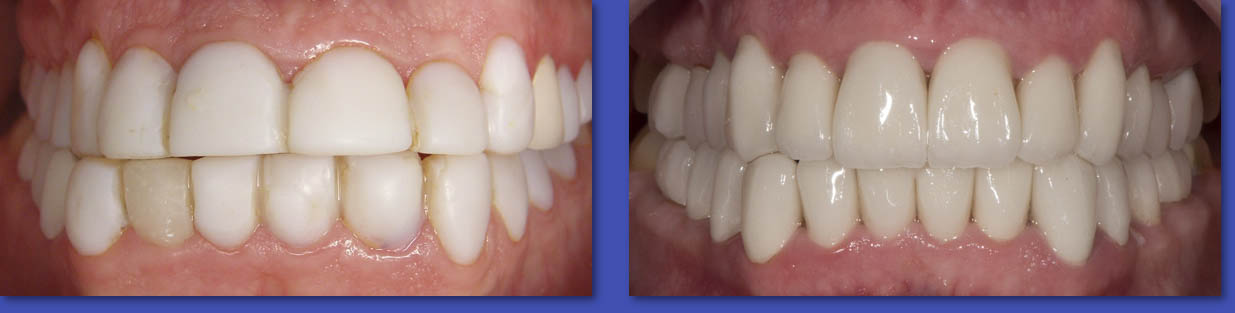

2. PERIODONCIA

La Periodoncia se dedica al tratamiento de las patologías que afectan a las encías y al hueso de soporte de los dientes. Las enfermedades principales son la Gingivitis y la Periodontitis, ambas se manifiestan principalmente por la inflamación y sangramiento de las encías. El tratamiento puede variar desde realizar una correcta técnica de cepillado y el uso de cinta dental, pasando por el destartraje (eliminación de sarro), o el pulido radicular en el caso de las periodontitis.

ANTES

DESPUÉS

Periodoncia